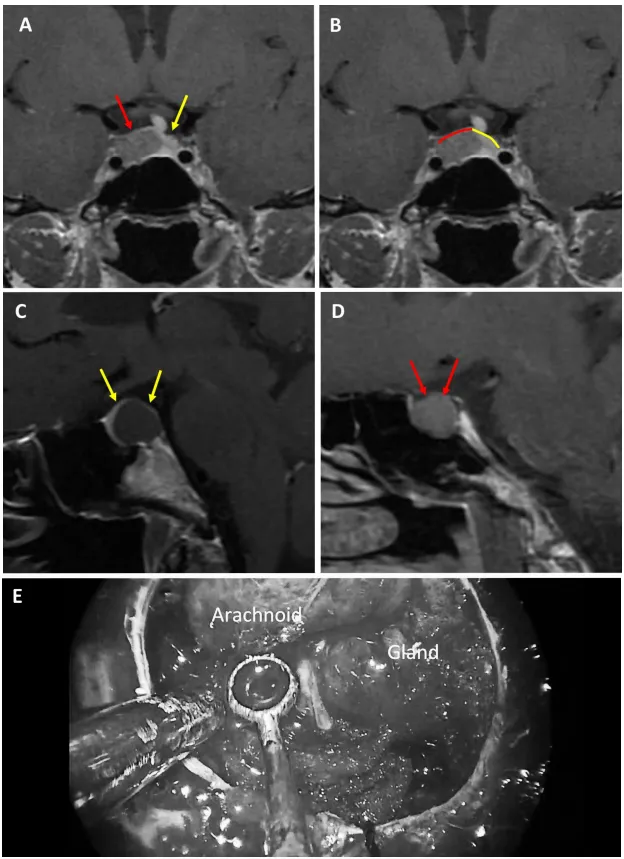

3. 薄弱型鞍隔屏障案例

图6展示59岁女性泌乳素腺瘤患者。a和b为术前MRI图像,红色箭头指示厚度小于1毫米的强化屏障区;c和d为术前MRI,红色标记线标示薄弱屏障位置;e和f为术中图像,显示由蛛网膜构成的屏障结构。